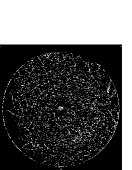

Figure 9: Ground truth (left) and segmentation result (right): (a) and (b) are the images from DRIVE dataset, (c) and (d) are the images from the STARE dataset

V-B Vessel Segmentation Performance

The segmentation performance of the proposed model on three public available datasets is given in Table IV. It can be observed that the proposed model can achieve more than 95%percent9595\% segmentation accuracy on the DRIVE, STARE and CHASE_DB1 datasets, with the highest accuracy score Acc=96.0%𝐴𝑐𝑐percent96.0Acc=96.0\% achieved in the DRIVE dataset. Some exemplary segmentation results are shown in Fig.9. When treating the unknown regions as background regions, AUC=0.833 of trimap is 2.6%percent2.62.6\% lower than the proposed model while Acc of trimap is similar to the proposed model. In addition, Se=0.679𝑆𝑒0.679Se=0.679 of trimap is 5.7%percent5.75.7\% lower than the proposed model. These observations show that trimap can already have good segmentation performance, which indicates that the selection of region features is very effective in segmenting blood vessels. From Table IV, it can be observed that the model with vessel skeleton extraction can achieve more than 5%percent55\% increase of Sensitivity𝑆𝑒𝑛𝑠𝑖𝑡𝑖𝑣𝑖𝑡𝑦Sensitivity and 2%percent22\% increase of AUC𝐴𝑈𝐶AUC compared with the model without vessel skeleton extraction while Acc𝐴𝑐𝑐Acc of the model with vessel skeleton extraction is similar to the model without vessel skeleton extraction, which demonstrates the effectiveness of vessel skeleton extraction.